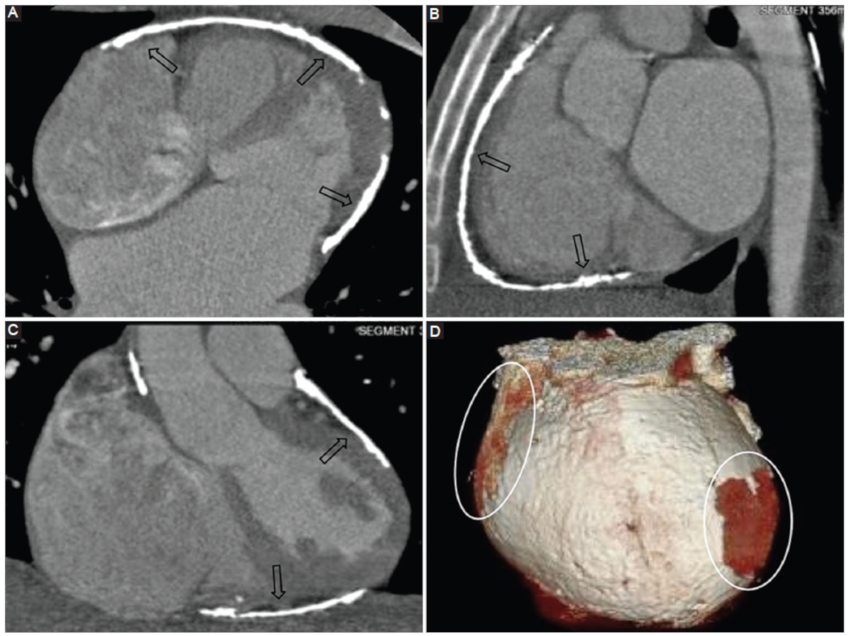

Pericarditis constrictiva

Representa una condición clínica resultante de una menor distensibilidad del pericardio2,14. Si bien su etiología es multifactorial, se asocia con mayor frecuencia al antecedente de pericarditis autoinmune, neoplasias del pericárdico y pericarditis bacteriana6,15.

Los síntomas clásicos de presentación son secundarios a falla diastólica, con signos de insuficiencia cardiaca derecha en ausencia de patología cardiaca subyacente6.

La TCMC presenta gran rédito para la identificación de la pericarditis constrictiva, así como también para discriminar los hallazgos de su principal diagnóstico diferencial que es la miocardiopatía constrictiva (Fig. 12). Cabe remarcar que si bien ambas entidades presentan similar escenario clínico, la pericarditis constrictiva es potencialmente tratable, a diferencia de la miocardiopatía constrictiva, que se asocia con un pronóstico desfavorable6.

Entre los hallazgos clásicos visualizados por TCMC se mencionan:

Engrosamiento pericárdico mayor a 4 mm. Este hallazgo resulta poco sensible, ya que puede presentarse con pericardio de grosor conservado16.

Calcificación de las hojas pericárdicas16.

Signos indirectos como reducción de volumen del ventrículo derecho de morfología tubular16.

Cabe mencionar que el engrosamiento y la presencia de calcificaciones resultan datos muy sugestivos de esta entidad, pero con limitada sensibilidad. En este sentido, Talreja et al. (16, en su serie de 143 pacientes con diagnóstico definitivo de pericarditis constrictiva, encontraron que un 18% de los casos se presentó con grosor pericárdico normal, y entre un 30-40% de los casos se presentó con calcificaciones pericárdicas.

La TCMC permite además una correcta evaluación prequirúrgica, considerando la pericardiectomía como tratamiento de elección2.